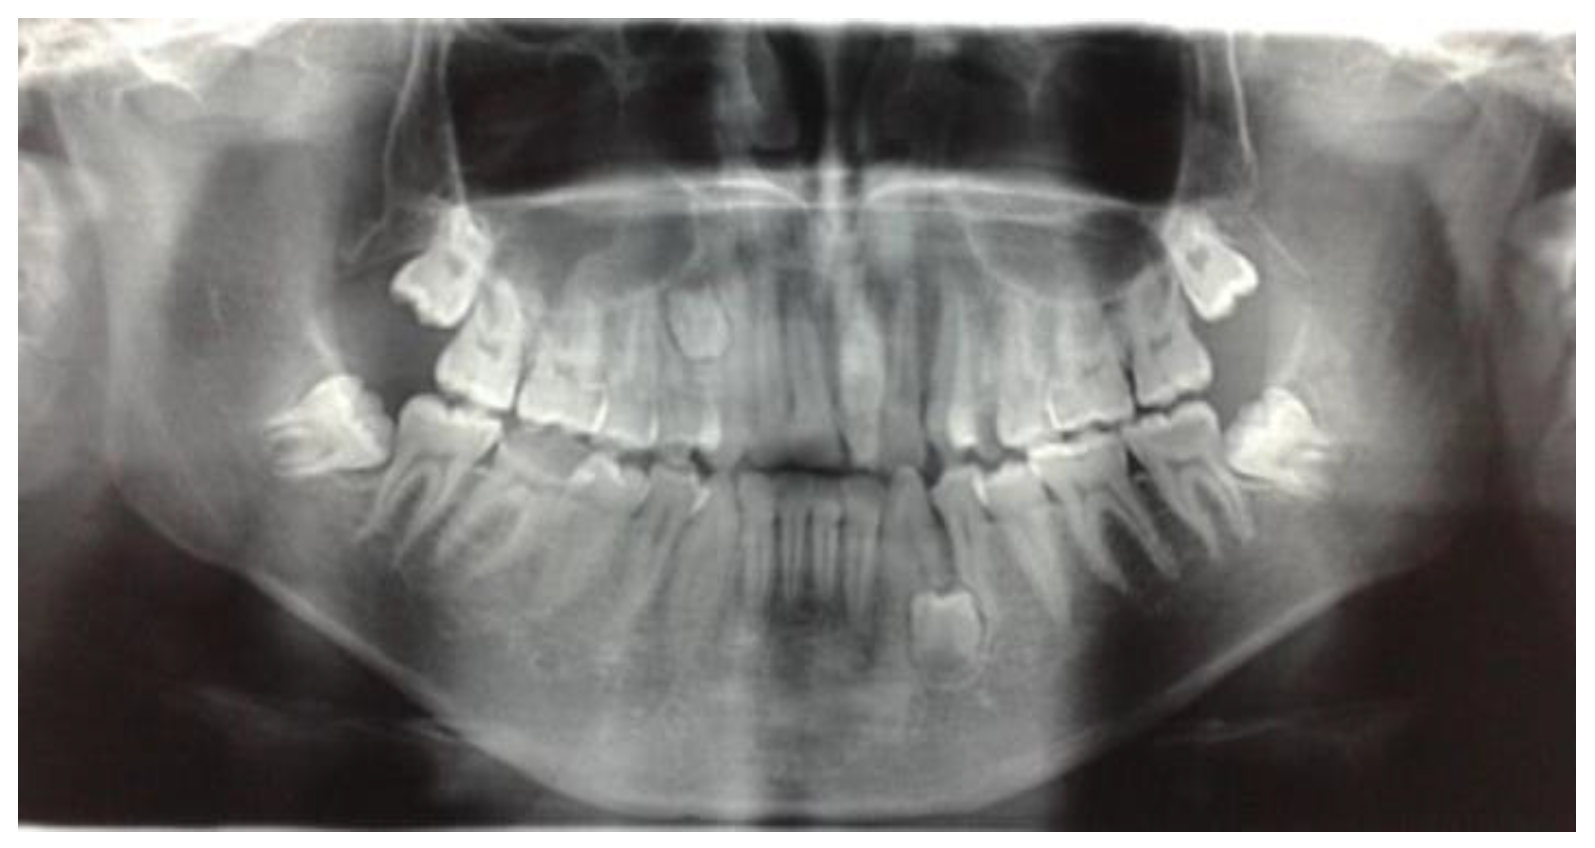

The presence of supernumerary teeth (Figure 1) is not a mere morphological curiosity but a potential source of diverse pathological complications [1,2,3,4].

Figure 1. Supernumerary teeth in the upper left quadrant.